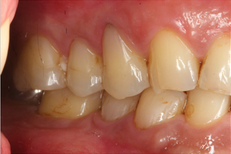

Mr NK, a 52-year-old male, presented with concerns of gradually shortening teeth and sensitivity to cold drinks. He also reported feeling self-conscious about his smile in photos. He is medically fit and has been using a night guard for his sleep-related grinding habit for the past year. Clinical examination revealed moderately worn dentition from erosion and attrition, along with mild crowding of the lower anterior incisors.

Intra-Oral Pictures (Before)

- Erosion severity: ACE Class Class III

- Reduced occlusal vertical dimension

- Mild crowding of lower anterior teeth